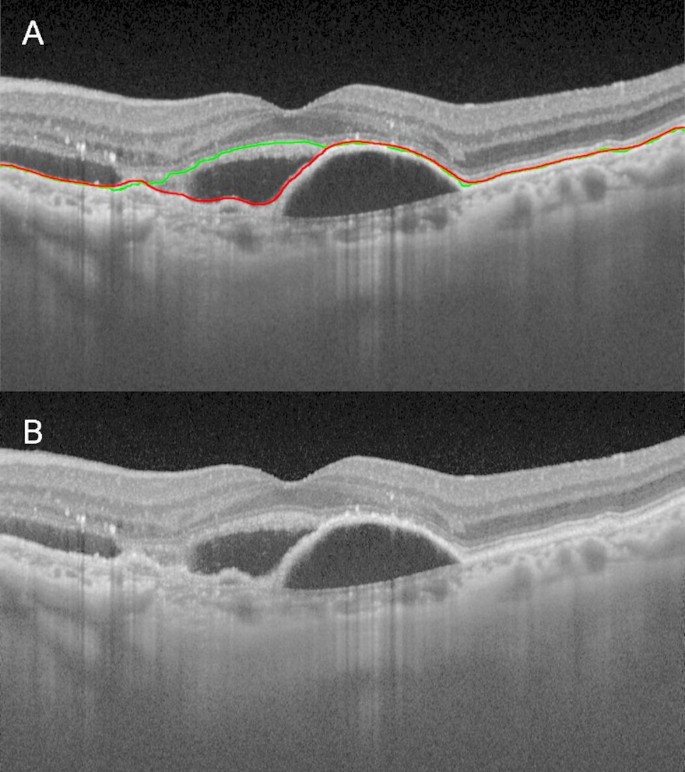

Representative horizontal optical coherence tomography (OCT) image obtained by Topcon’s automated segmentation algorithm showing a segmentation artifact and its corresponding image. (A) The green line shows the retinal pigment epithelium (RPE) line identified by Topcon’s automated segmentation algorithm of age-related macular degeneration (AMD). The red line shows the RPE line identified by the proposed technology method. In this AMD OCT image, there are parts where Topcon’s automated segmentation algorithm cannot correctly detect the RPE line, but the proposed technology method can correctly detect it. (B) Original image corresponding to (A).

The median MAE values obtained for the AI method and Topcon’s automated segmentation algorithm in RPE detection for each image group were as follows: AMD, 2.18 and 4.79; DR, 1.69 and 3.17; ERM, 1.50 and 2.67; BRVO, 1.86 and 2.98; and normal, 1.59 and 2.28. MAEs were significantly better with the proposed technology method than with Topcon’s automated segmentation algorithm in all groups (P < .001; Table 2). Furthermore, the range in MAE improvement was smallest in the AMD group (Figs. 2 and 3).

Representative horizontal optical coherence tomography (OCT) image of retinal pigment epithelium (RPE) identification and its corresponding image. (A) Representative horizontal OCT image of the left eye of age-related macular degeneration (AMD) showing the identification of RPE using the proposed technology and conventional methods. The green line shows the RPE line identified by the conventional method. The red line shows the RPE line identified by the proposed technology method. In this AMD OCT image, there are parts where Topcon’s automated segmentation algorithm could not correctly detect the RPE line, but the proposed technology method did. (B) Original image corresponding to (A).